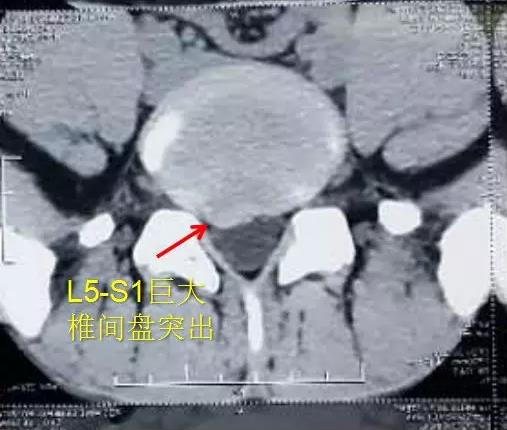

小刘本是村里很有前途的孩子,两年前凭借着自身努力过五关斩六将,挑灯夜读,闻鸡起舞,在河南百万高考大军中脱颖而出,考入一流大学——素有西北小清华之称的新疆石河子大学,能从农村考入“211”重点院校必将成为父母的骄傲,邻里教育孩子的榜样,可是就在春节前夕的一天,小刘突然腰疼的下不了床,双下肢疼痛剧烈,就连简单的端坐都是极大的奢侈。这下急坏了父母,带着小刘四处寻医,本以为吃点药、输点液、或者吃点止疼药物即可缓解,可是父母还是低估了小刘的疾病。从村里到镇上,从县里到市里,问题都没有得到解决,而且疼痛愈来愈烈,在当地某知名医院诊断为“极外侧型腰椎间盘突出症”。医生告知小刘的父母小刘需要开刀手术,费用大概需要7万元,住院15日左右,术后又需长时间康复治疗。

▲ 小刘在当地医院拍摄的X光片和CT片